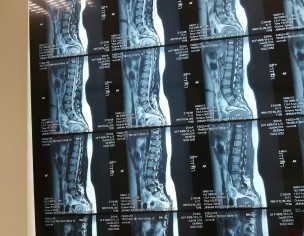

Attaching my MRI reports (MRI was in July). Everyone told me there is nothing serious just go for painkillers and physiotherapy. I was taking naproxen and was on physiotherapy from last 2 months. But still, there is no improvement. Sometimes I face severe back pain. So can someone please guide me what to do now? Please don't suggest me any treatment which is expensive as already invested a lot but all in vain. Is this disc herniation? Is it curable? I am seriously worried about it.

Cant attach my MRI report as there is no Attach option

Attach Photo here: